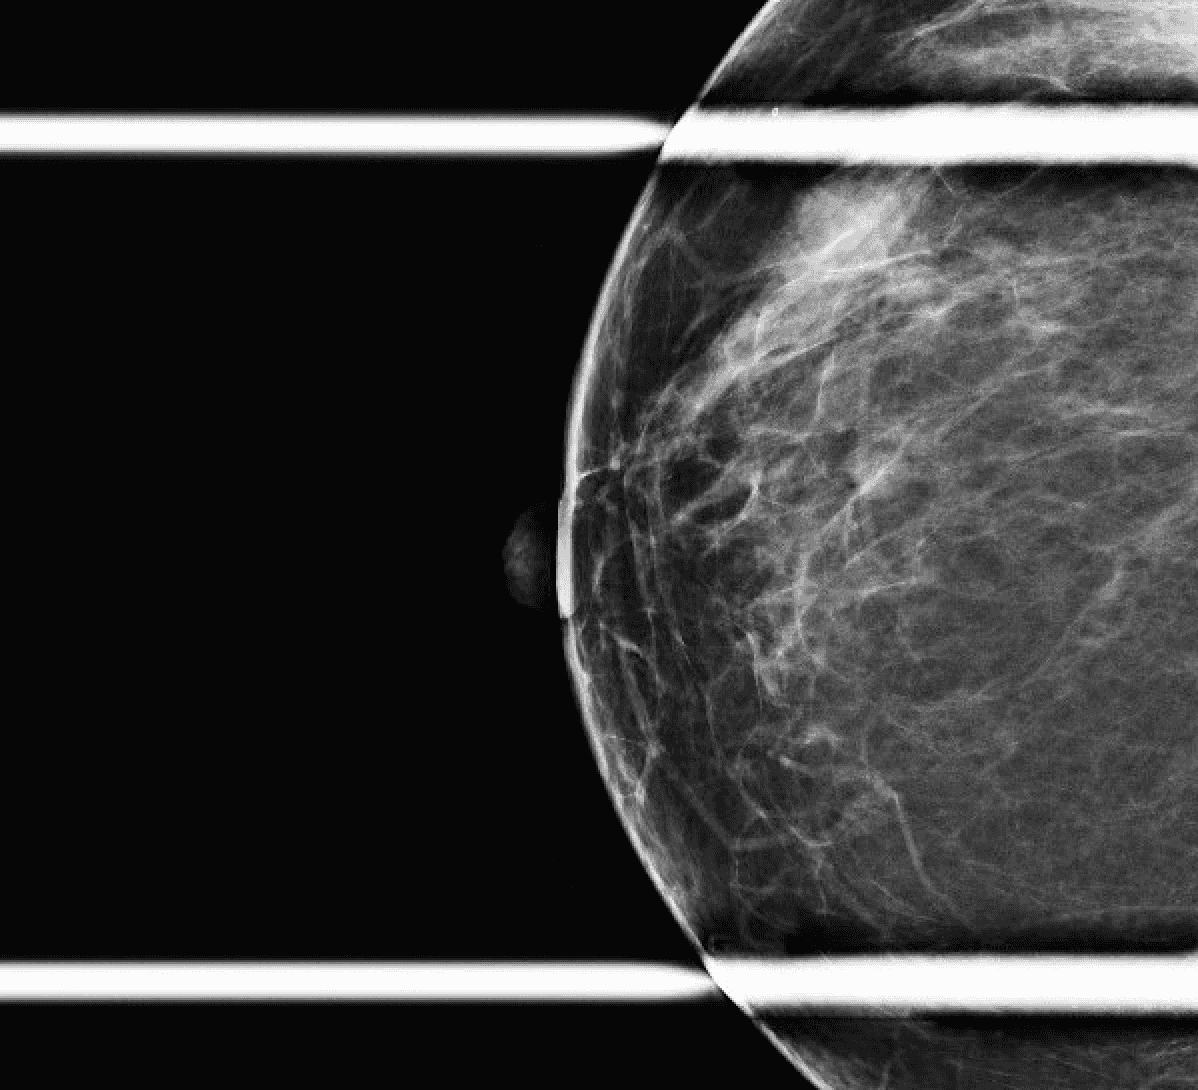

Patient is a 46-year-old premenopausal female with no other contributing past medical or surgical history who presented initially to the breast surgery clinic after her annual screening mammogram discovered a nonpalpable right breast mass measuring 0.6 x 0.8 x 0.7 cm at 11 o’clock (oc), 1 cm from the nipple (FTN) (Figure 1). She had three previous screening mammograms without any notable findings. The screening mammogram was declared inconclusive (BI-RADS 0), and a breast ultrasound was completed with similar findings. Further discussion with the patient revealed that there had been some bloody discharge seen in the right side of her bra over the last few months, but no other concerns or symptoms. Given the inconclusive imaging findings, it was decided to perform a diagnostic mammogram for a more specific assessment (Figures 2a and 2b) following an ultrasound-guided core-needle biopsy and localizing clip placement for a tissue diagnosis (Figure 3). Pathology revealed an intraductal papilloma with ductal hyperplasia and apocrine metaplasia without atypia. Given her continued bloody nipple discharge, there was concern for possible underlying premalignant cells (discussed more later); thus, it was recommended that the patient undergo partial mastectomy. The mass remained nonpalpable; therefore, a Savi Scout would be placed just before operative intervention to help localize the area of concern.

Figure 2a. Post-biopsy diagnostic mammogram. Right mediolateral oblique view, including an enlarged area for better detail of the coiled biopsy clip in the area of concern (arrow).

Figure 2b. Craniocaudal view of the post-biopsy diagnostic mammogram. Including a closer image of the area with the coiled biopsy clip (arrow).